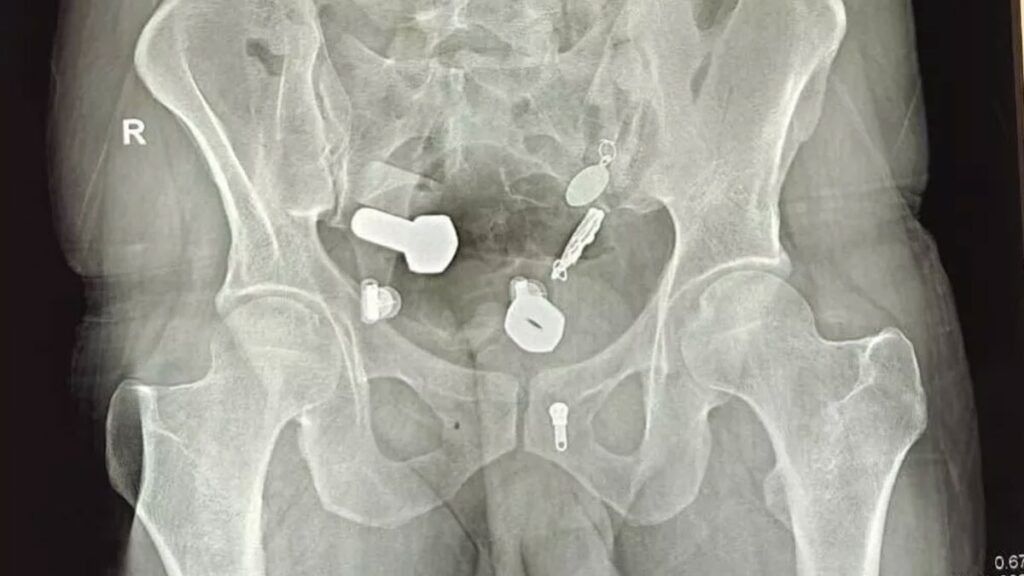

Hindistan’ın Jaipur kentindeki Sawai Mansingh Hastanesi’ne 9 Ekim’de kaldırılan hasta, günlerdir süren mide ağrısı nedeniyle yemek yiyemediğini ve su içemediğini söyledi. Yapılan taramada doktorlar, adamın yemek borusunda bir kol saati, bağırsaklarında ise metal parçaları, cıvata ve somunlar olduğunu fark etti. ÜÇ SAAT SÜREN AMELİYATA ALINDI Cisimler önce endoskopiyle çıkarılmak istense...